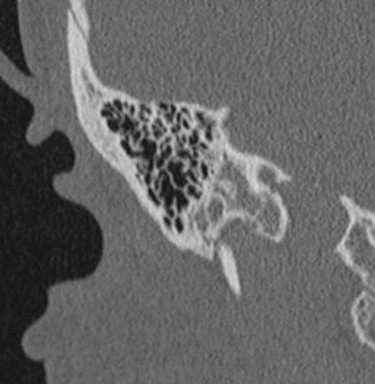

Опухоли эндолимфатического мешка доброкачественные, медленнорастущие, двухсторонние связаны с болезнью Гиппель-Линдау, относящейся группе факоматозов. При КТ видна костная эрозия верхушки пирамиды, а при МРТ головного мозга с контрастировавшем образование хорошо усиливается.

Холестеатомы (эпидермоидные кисты) часто встречаются в области верхушки пирамиды. Их отображение на МРТ зависит от примеси холестерола.

Вестибулокохлеарный нерв (VIII) состоит из 4 пучков. Опухоли происходят обычно из вестибулярной его части. Шваннома - инкапсулированная доброкачественная (градация 1) опухоль, происходящая из дифференцированных неопластических шванновских клеток оболочек периферических нервов. Невриномы ММУ составляют около 3% опухолей головного мозга. Часть шванном (двухсторонние слуховых нервов) связана с НФ 2 типа. Пик частоты между 40 и 60 годами. Растут медленно и крайне редко малигнизируются. Клинические проявления связаны с нарушением функции нерва и компрессией ствола. Шваннома может происходить из любого отрезка по ходу нерва и хорошо прослеживается при МРТ области ММУ. Невринома видна как на Т2-взвешенных, так и на Т1-взвешенных МРТ в виде округлого образования. Невриномы хорошо и равномерно усиливаются после МРТ с введением контрастного вещества. Невриномы области цистерны могут иметь компонент во внутреннем слуховом проходе, особенно, хорошо видимый при МРТ головного мозга с контрастированием. Изредка встречаются невриномы полностью расположенные внутри канальца. Они составляют наибольшую диагностическую сложность при МРТ, требуют тонких срезов и контрастирования. Менингиомы ММУ обычно типично расположены и при МРТ имеют характерную форму и типичные черты при МРТ с контрастированием. Однако редко встречаются внутриканальцевые менингиомы. При МРТ они неотличимы от неврином. Холестеатомы при МРТ имеют смешанную интенсивность сигнала, в зависимости от их содержимого. На диффузионно-взвешенных МРТ холестеатомы обычно яркие.

МРТ головного мозга наиболее информативна в плане выявления опухолей мостомозжечкового угла и кист этой области. Некоторое патологии, такие как расширение водопровода и лабиринтит также хорошо видны при МРТ. КТ лучше демонстрирует состояние внутреннего уха.